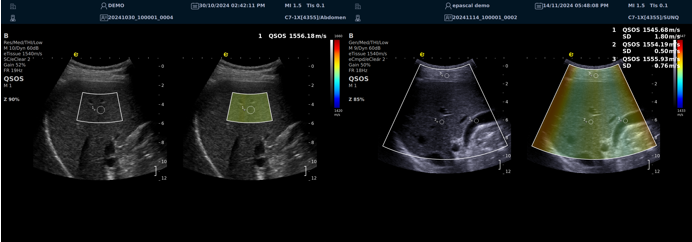

QSOS声速定量成像

测量原理

QSOS声速成像技术利用声波在组织中的传播速度差异性,计算不同位置的声速值,反映组织的物理特性。

成像过程

利用超声探头发射超声波脉冲,分析反射信号的时间延迟,确定声波传播路径和速度,构建声速分布图像。

图像显示

QSOS技术采用彩色编码显示声速图像,不同颜色代表不同声速值,便于医生识别病变部位和测量。

25fb8cb17586b86e5d915a2be3025a2.png

技术优势

?精准定量反映组织特性,成像更敏锐?彩色编码直观显示,轻松发现异常?捕捉声速差异,早期、微小病变更易察觉

肌骨22.png

肌骨领域的应用

?精准定位损伤部位?判断损伤严重程度?监测肌肉营养?评估肌少症?骨质疏松评估